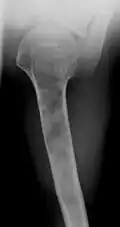

X-ray showing enchondromas localized in the humerus of a 37-year-old patient affected with Ollier disease -

Abnormal bone growth such as shortening or thickening and deformity may be observed in patients of Ollier disease. These bone lesions are visible at birth using radiography but are usually not screened or examined for until clinical manifestations present during early childhood. However, some patients may exhibit no signs of any symptoms.[1] One study found thirteen to be the mean age of diagnosis in patients with Ollier disease. In an X-ray, there would normally be the presence of several homogeneous lesions of an oval or elongated shape with bone edges that are slightly thickened.[3] With age, these lesions may calcify and appear as diffusely minute spots or stippled. Fan-like septations or streaks would be indicative of the presence of several enchondromas. Early detection and consistent and repeated monitoring is important in order to prevent and treat any potential bone neoplasms.